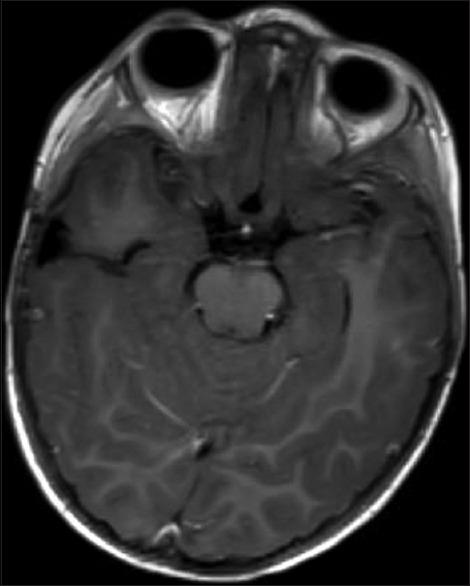

Choroid plexus tumors (CPT) in the pediatric population are usually discovered in symptomatic patients often with symptoms of increased intracranial pressure, with hydrocephalus as the most common presentation, along with seizures, subarachnoid hemorrhage, or focal neurological deficit. Most CPTs are found to be benign choroid plexus papillomas (CPP), whereas a small number are intermediate and malignant choroid plexus carcinomas (CPC). Total surgical resection is the established definitive treatment for symptomatic CPP.

We describe a young female who was found to have an incidental CPT during workup for recent head trauma without neurological deficits or hydrocephalus. She underwent a surgical operation to remove the tumor successful, with 1-year follow-up showing no recurrence and normal developmental milestones.